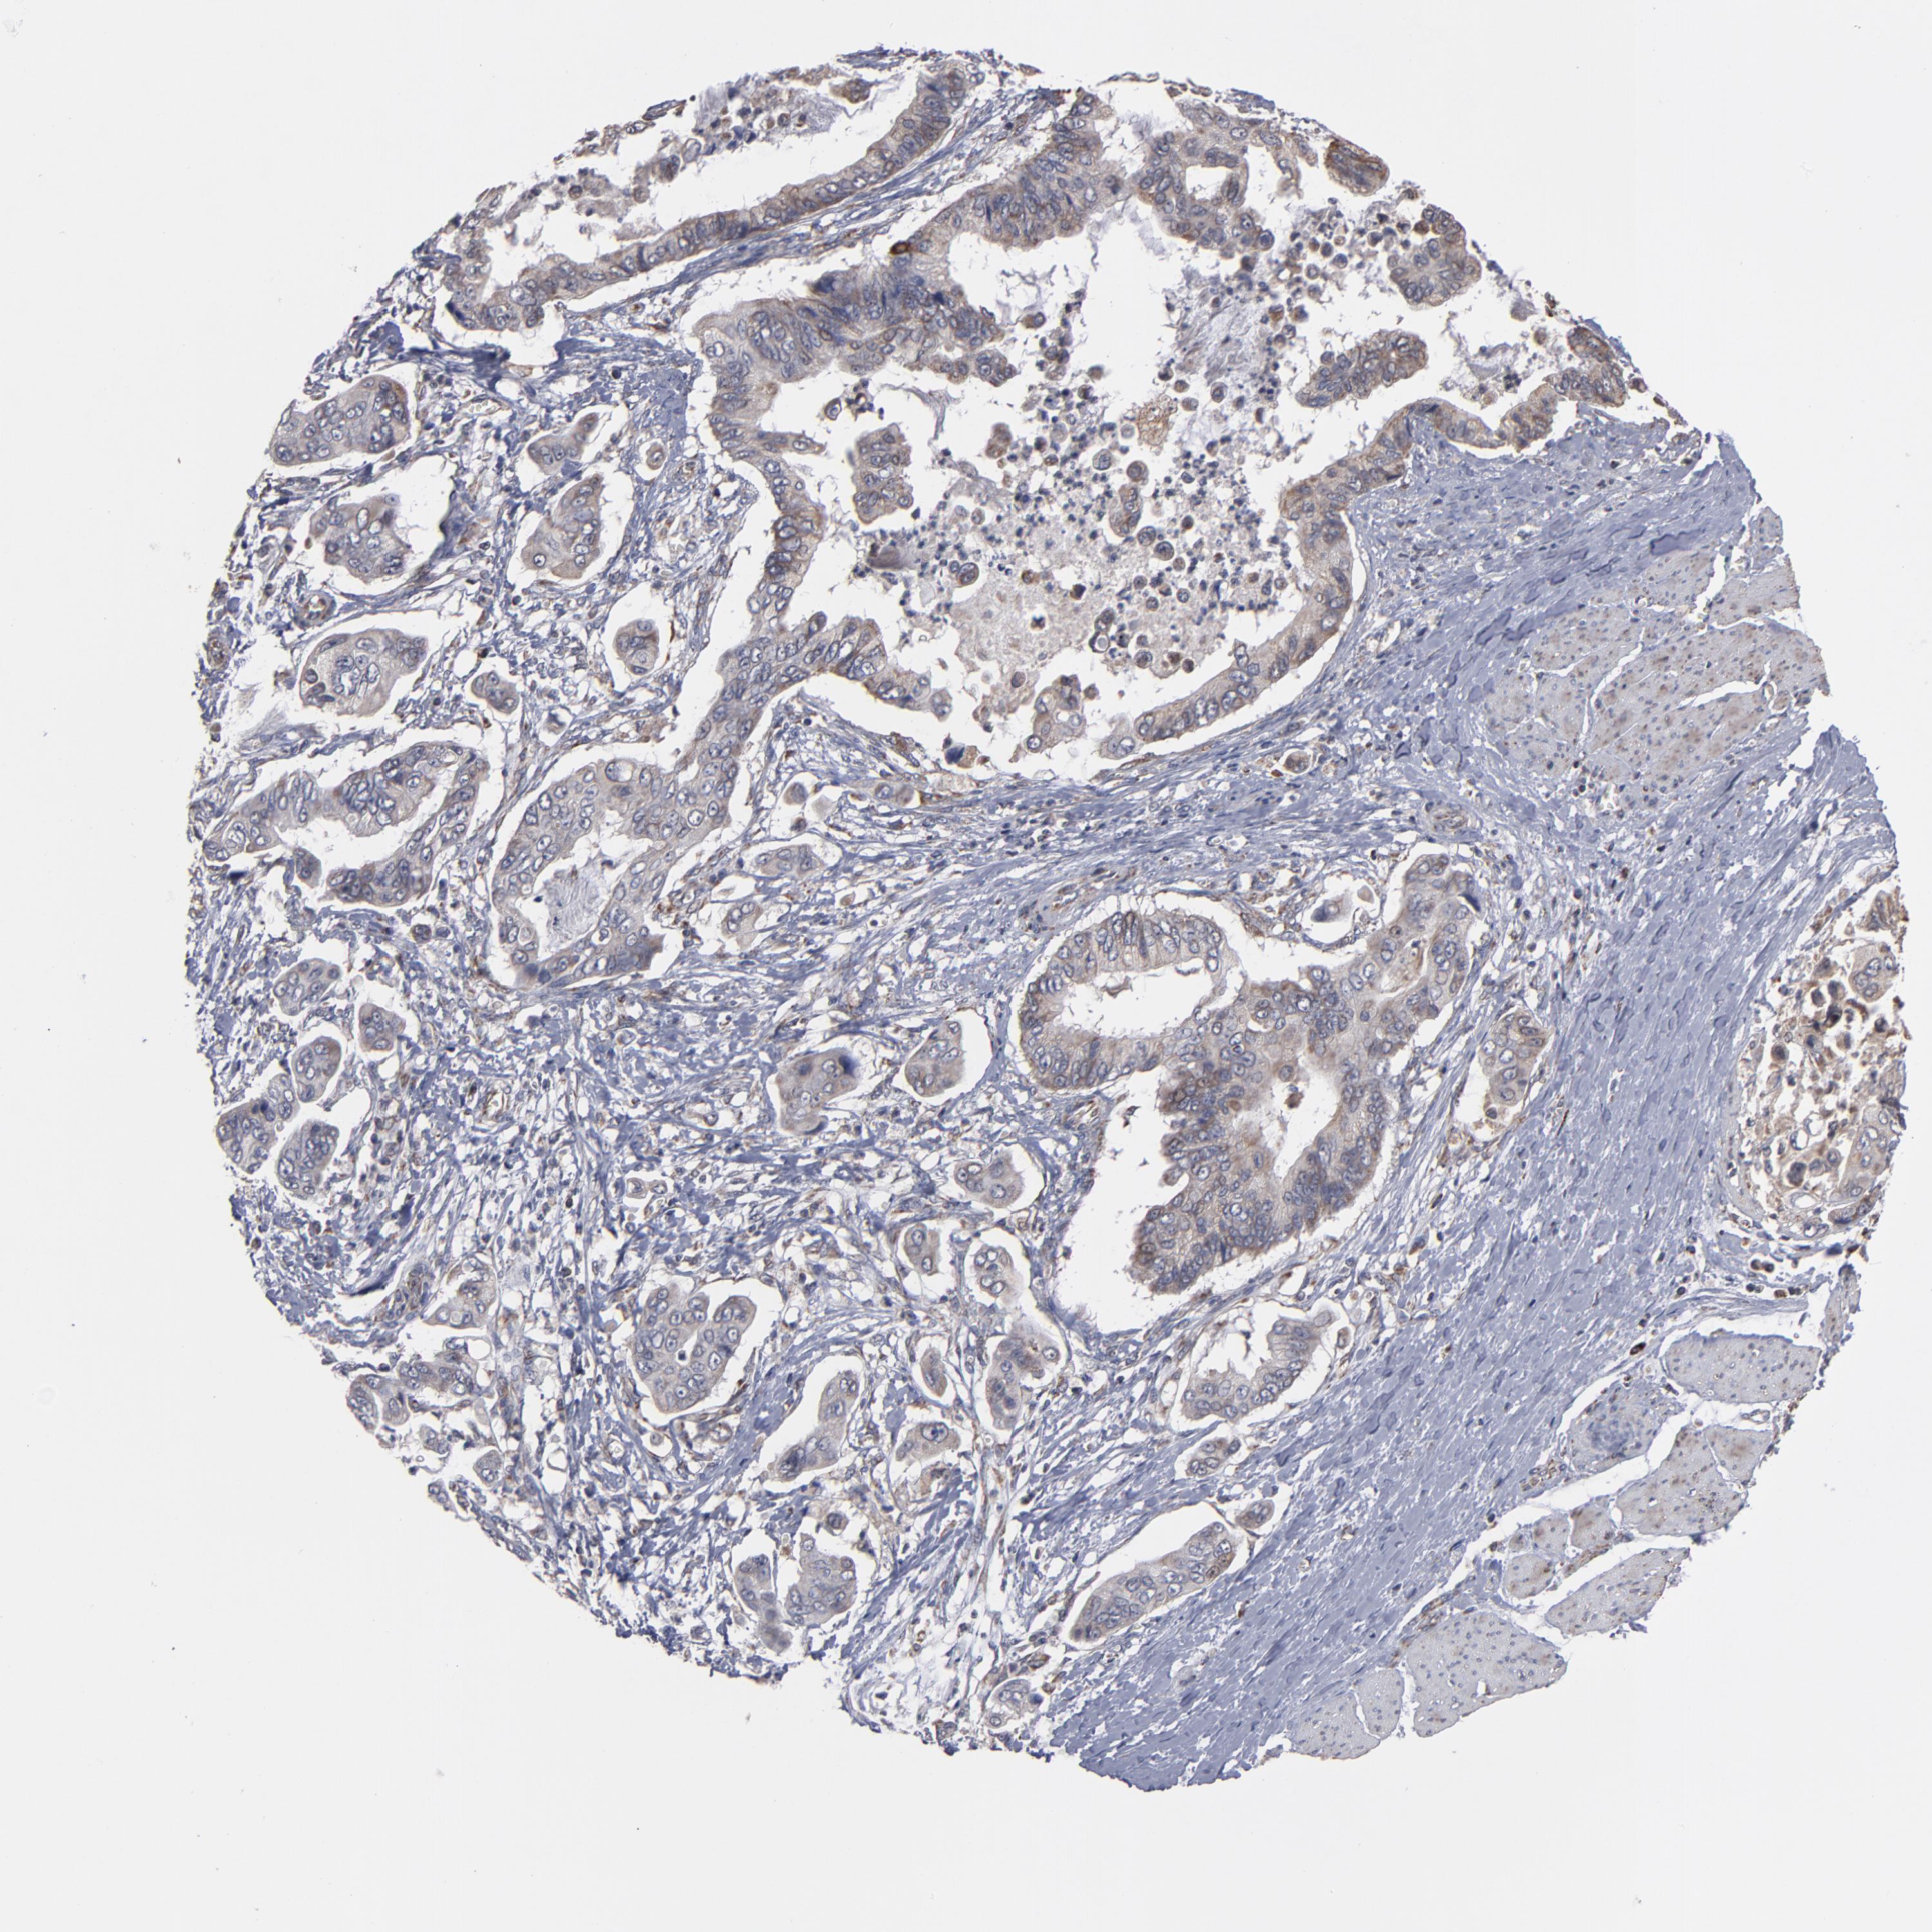

STOMACH CANCER - Protein expressioni

A mouse-over function shows sample information and annotation data. Click on an image to view it in a full screen mode. Samples can be filtered based on level of antibody staining by selecting one or several of the following categories: high, medium, low and not detected. The assay and annotation is described here.

Note that samples used for immunohistochemistry by the Human Protein Atlas do not correspond to samples in the TCGA dataset.

Antibody stainingi

Antibody staining in the annotated cell types in the current human tissue is reported as not detected, low, medium, or high, based on conventional immunohistochemistry profiling in selected tissues. This score is based on the combination of the staining intensity and fraction of stained cells.

Each image is clickable and will lead to virtual microscopy that enables deeper exploration of all samples and also displays staining intensity scores, fraction scores and subcellular localization as well as patient and tissue information for each sample.

Antibody HPA002893

Staining

High

Medium

Low

Not detected

Intensity

Strong

Moderate

Weak

Negative

Quantity

>75%

75%-25%

<25%

None

Location

Nuclear

Cytoplasmic/membranous

Cytoplasmic/membranous,nuclear

Adenocarcinoma, NOS